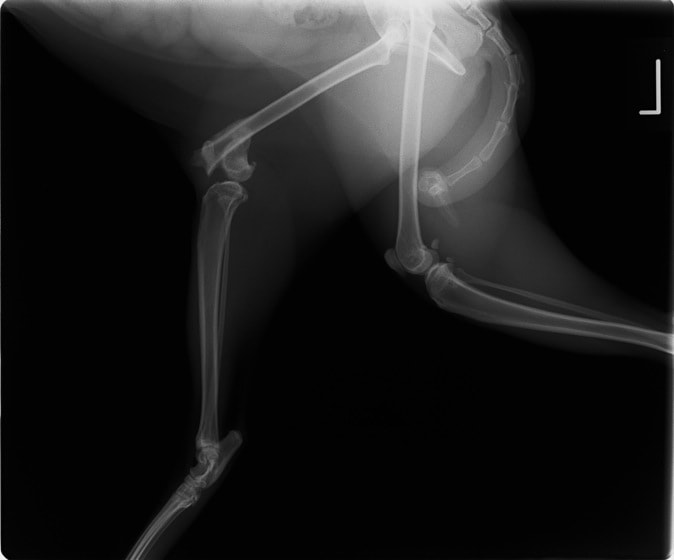

ペルシャ猫 11ヶ月齢 雄

他院にて左大腿骨遠位の成長板骨折(salter-harrisⅠ型)が認められており、治療相談を目的として来院。当院にて、キルシュナーワイヤーを用いたピンニングにより骨折部位の整復を行いました。術後の経過は良好で、現在も経過観察中です。

術前レントゲン

術後レントゲン